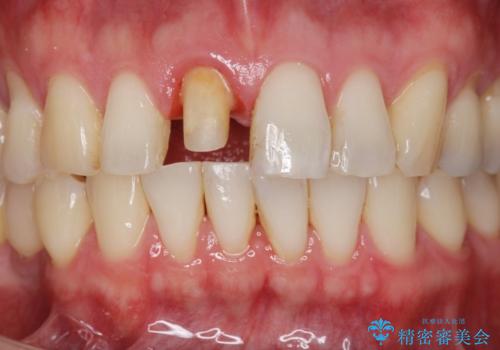

- 治療計画

- 前歯の変色が気になり審美障害の改善を求めて来院されました。

根管治療に伴う歯の色調変化はよく見られる所見です。

セラミッククラウン製作を行い審美性の改善を計画します。

- 15.4万円(仮歯・ファイバーコア・ジルコニアクラウン)費用は治療当時の料金となります